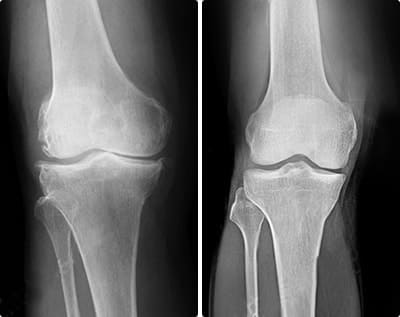

Las lesiones pueden variar en complejidad, pero se pueden agrupar en dos tipos: musculares y articulares. Esguinces, desgarros, osteoartritis crónica. Los riesgos son inevitables si no te proteges a tiempo.

El fútbol es un deporte extremadamente traumático. Las rodillas, las pantorrillas y el pie están constantemente en riesgo. Lo pasé por todo durante mi carrera: desde la distensión de los músculos de la pierna hasta el daño del menisco. Es imposible defenderse de todo, siempre tengo Сortitron a mano durante el período de rehabilitación.